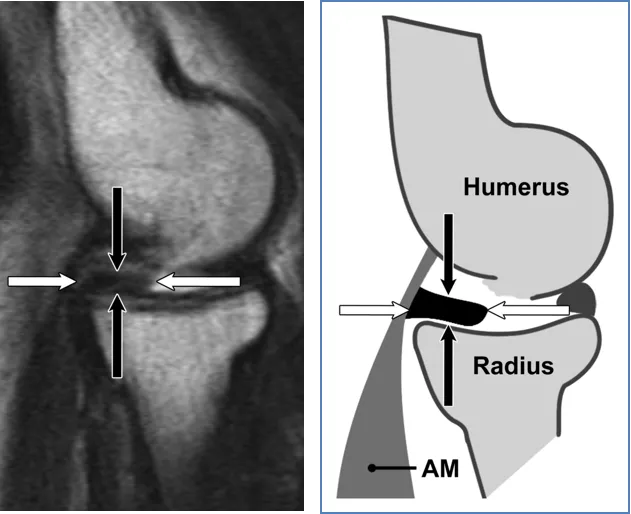

(a) 40岁男性横轴位中等加权脂肪抑制磁共振成像显示环状韧带与桡骨切迹的后方(白色箭头)和前方(黑色箭头)连接及其绕桡骨头的路径。(b) AL对应示意图显示AL在径向缺口上的后部(白色箭头)和前部(黑色箭头)连接。AM = 无尾肌,BM = 肱肌,BT = 肱肌腱。